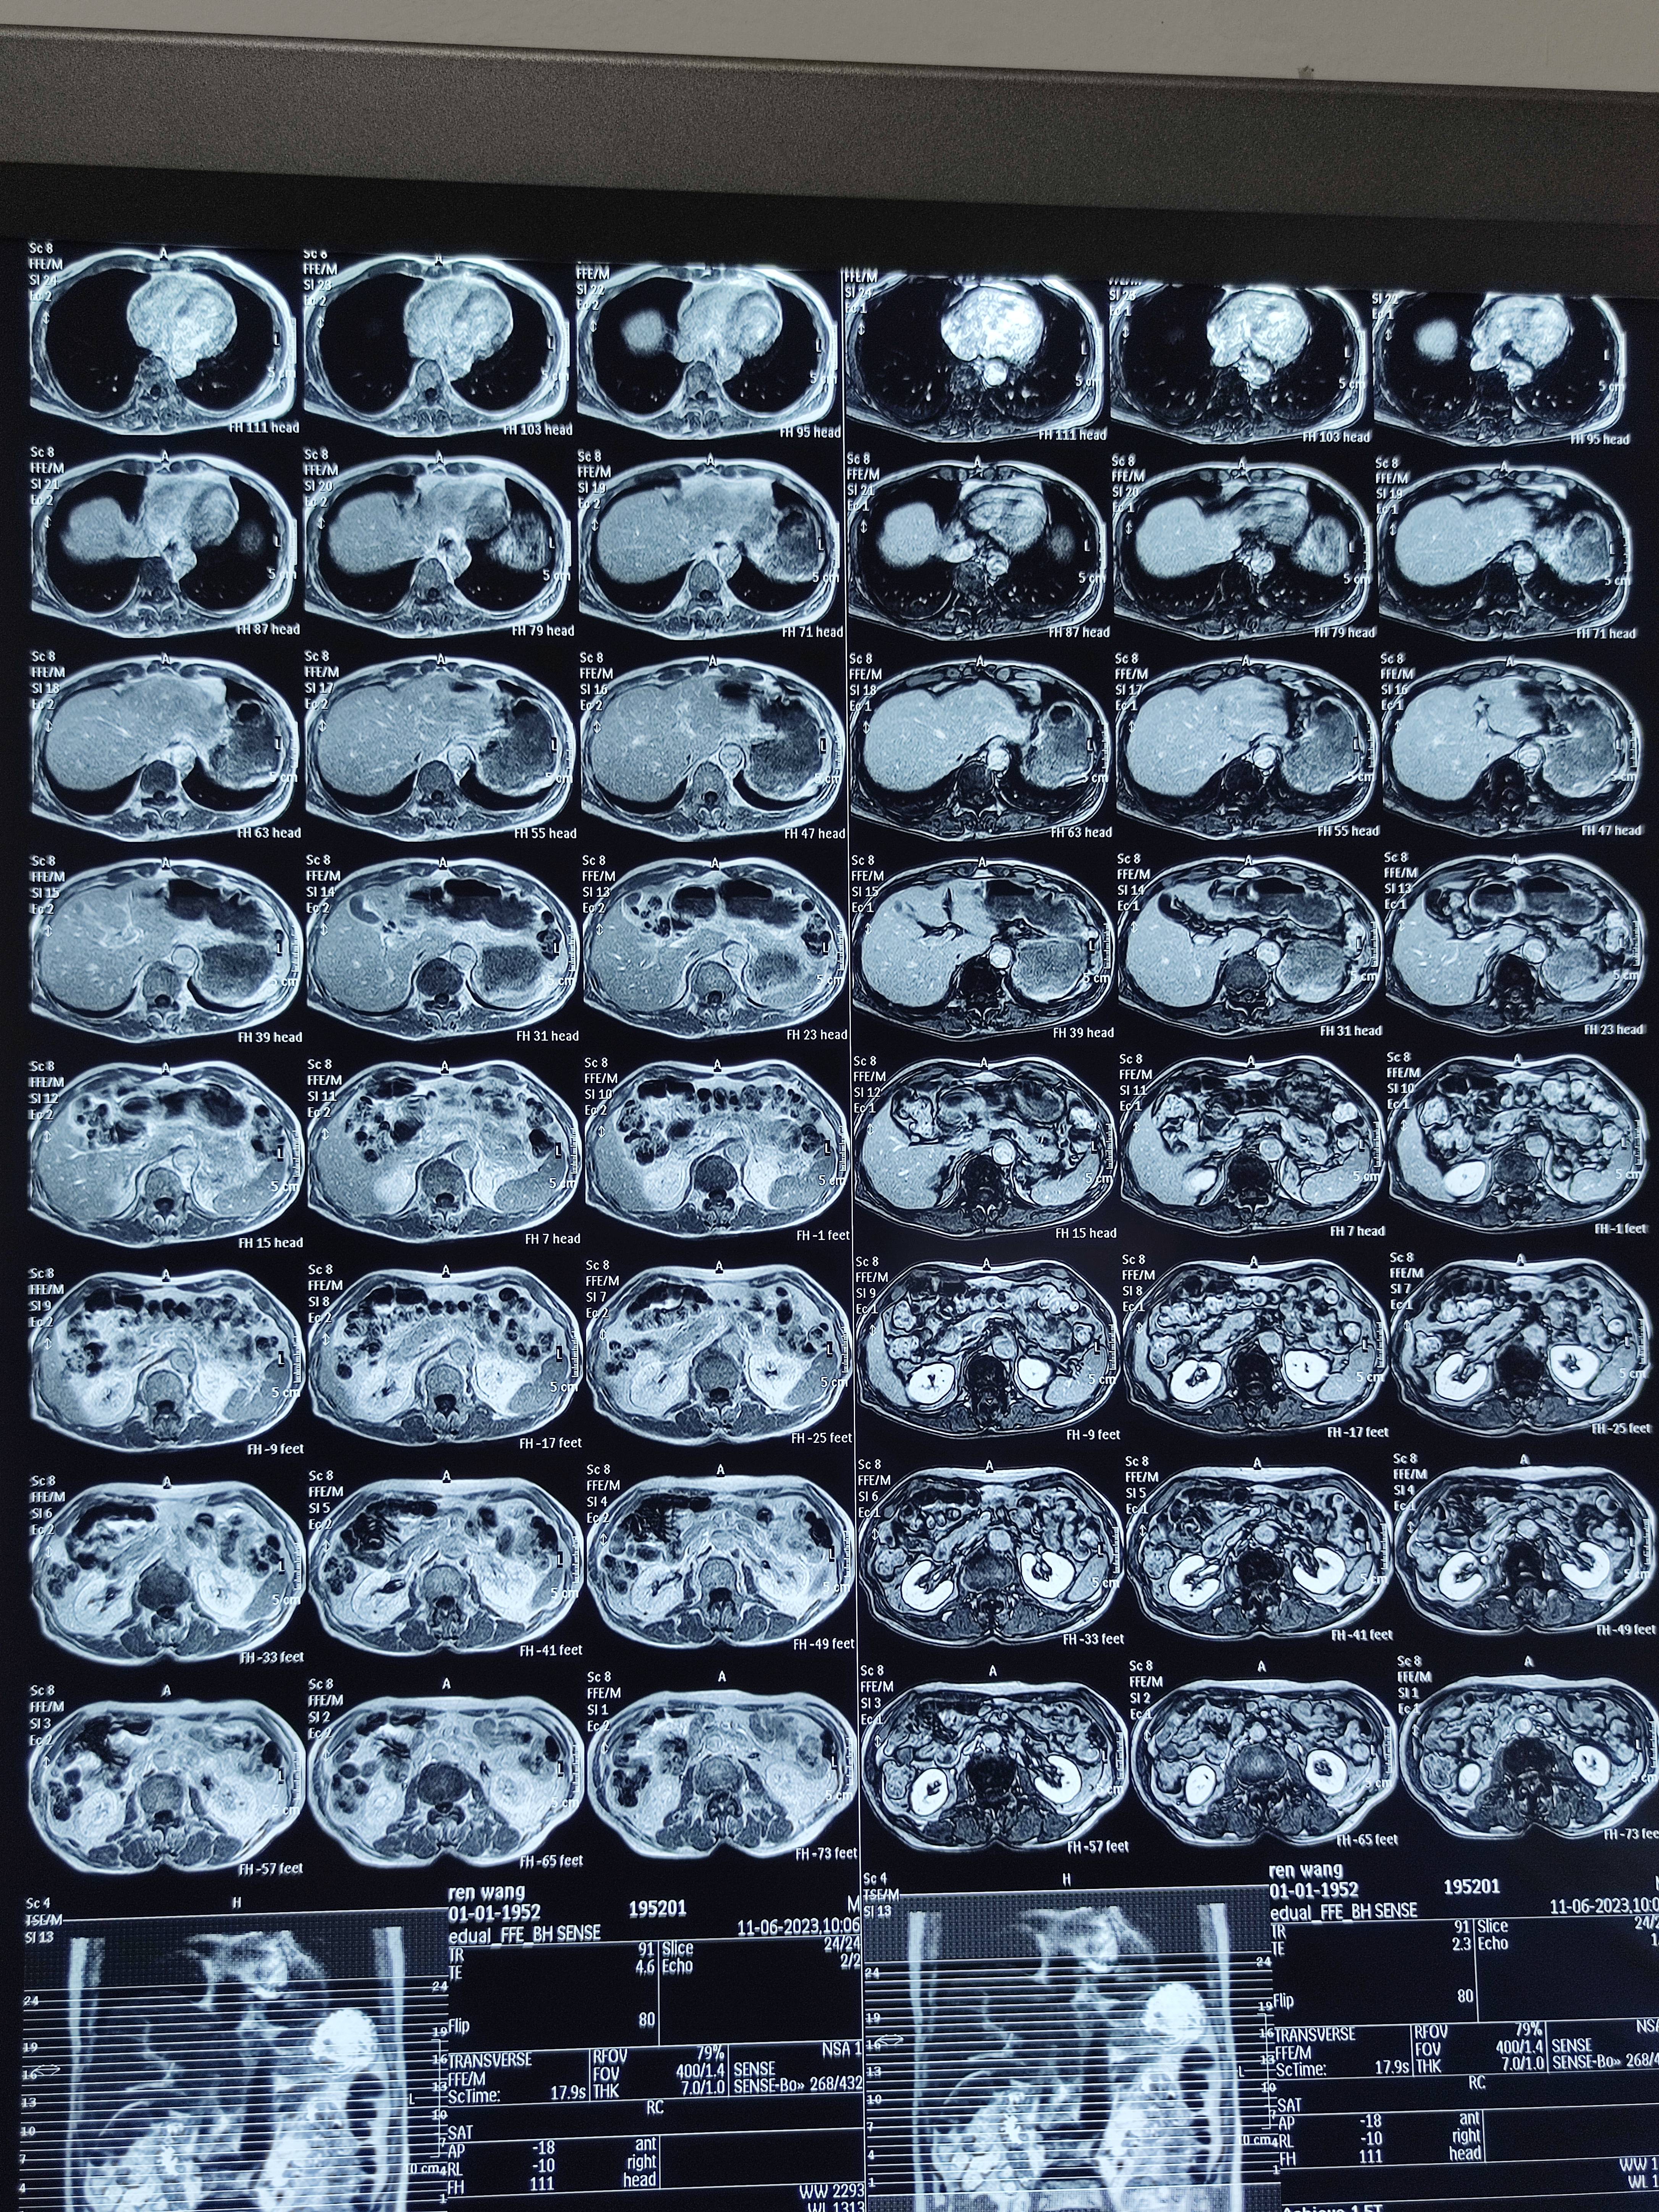

四月份癌胚抗原还是5.6,这个月到8了,持续升高。做了核磁增强,左侧桥小脑角哪有个地方不确定。肝脏核磁平扫弥散有两个点状高信号,转移也排不了,胃肠镜正常,左颈部有个变圆的淋巴结,保险点是不该加个化疗药了?咨询了陈波主任,等结果的吧!图片